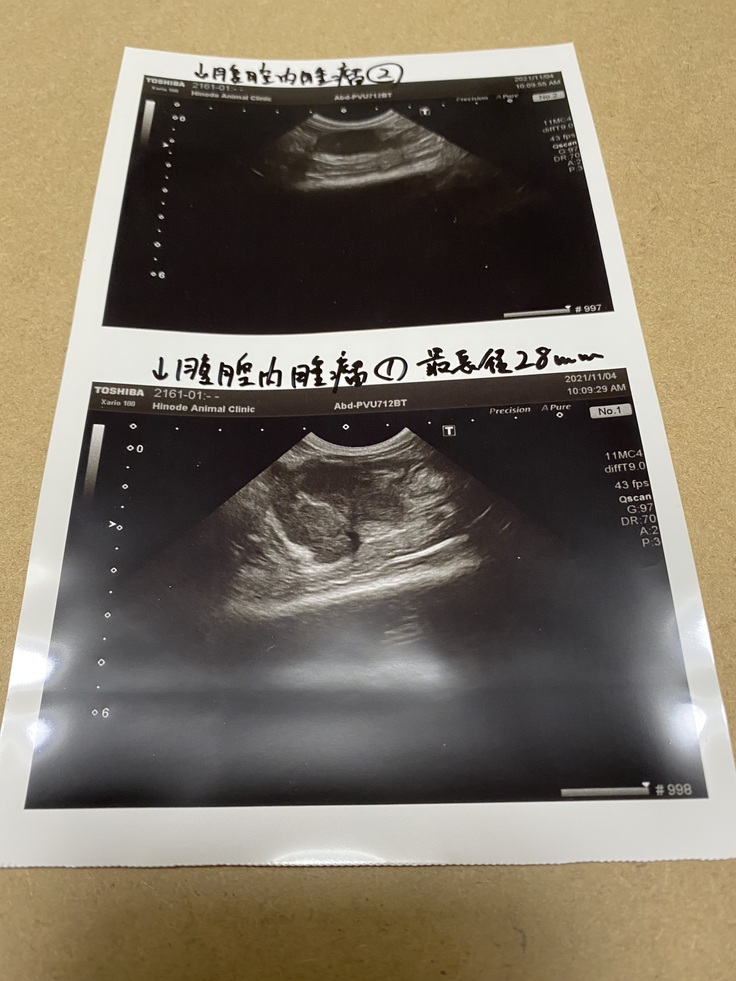

10月頃より元気がなくなり、常に寝ているような状態で下痢もひどくなっていきました。何度か動物病院に連れて行きましたが、下痢止めをいただくだけで一向に良くならず、セカンドオピニオンで他の動物病院へ11月5日に連れて行ったところ、検査結果が出るまでわからないが高い確率でFIPではないかと診断されました。その際に初めてFIPという病気を知り、数日から数ヶ月の間には必ず死んでしまうという急な余命宣告をされ、ショックで涙が止まりませんでした。

また、2週間毎の検査結果でもしこりが小さくなってきていると言われ、少し安心しました。それ以降のお薬は郵送にて購入して治療を続けております。